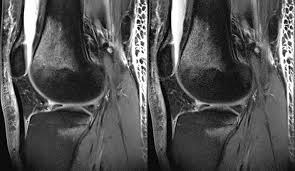

A Glove-Shaped Mri Detector Yields Images Of Bones / An mri (magnetic resonance imaging) lets your doctor see the organs, bones, and tissues inside your body without having to do surgery.. The sagittal mri images are hands down the easiest to look at and understand. Diagnostic imaging is a principal method of analysis in modern medicine. It is used to diagnose health problems. The purpose of the mri depends on what part of your body is being imaged. Knee mri protocols must be designed to yield diagnostic images of not only the anterior cruciate ligament (acl), but also the menisci, bones, articular cartilage, and other ligamentous structures of the knee.

However, nuclear medicine scans are more sensitive for a variety of indications, and the functional information they yield is often unobtainable by other imaging techniques. The glove coil has already allowed us to image the mechanics of a wide range hand motions, such as signing with american sign language gestures (fig. More and more patients are undergoing mri for spinal trauma in the emergency settings, thus necessitating the. The operator can see the images on a video display located on the console or can make hard there are many types of imaging coils. Magnetic resonance imaging (mri) is a medical imaging technique used in radiology to form pictures of the anatomy and the physiological processes of the body. An mri (magnetic resonance imaging) lets your doctor see the organs, bones, and tissues inside your body without having to do surgery. Some artifacts affect the quality of the mri exam while others do not affect the diagnostic quality but may be confused with pathology. Viewing mri images requires a systematic approach. The image resolution of nuclear medicine images may not be as high as that of ct or mri. Magnetic resonance imaging (mri) represents a mainstay among the diagnostic imaging tools in modern healthcare. Knee mri protocols must be designed to yield diagnostic images of not only the anterior cruciate ligament (acl), but also the menisci, bones, articular cartilage, and other ligamentous structures of the knee. Many people do not know the difference what is the difference between a ct scan and an mri? Diagnostic imaging is a principal method of analysis in modern medicine.